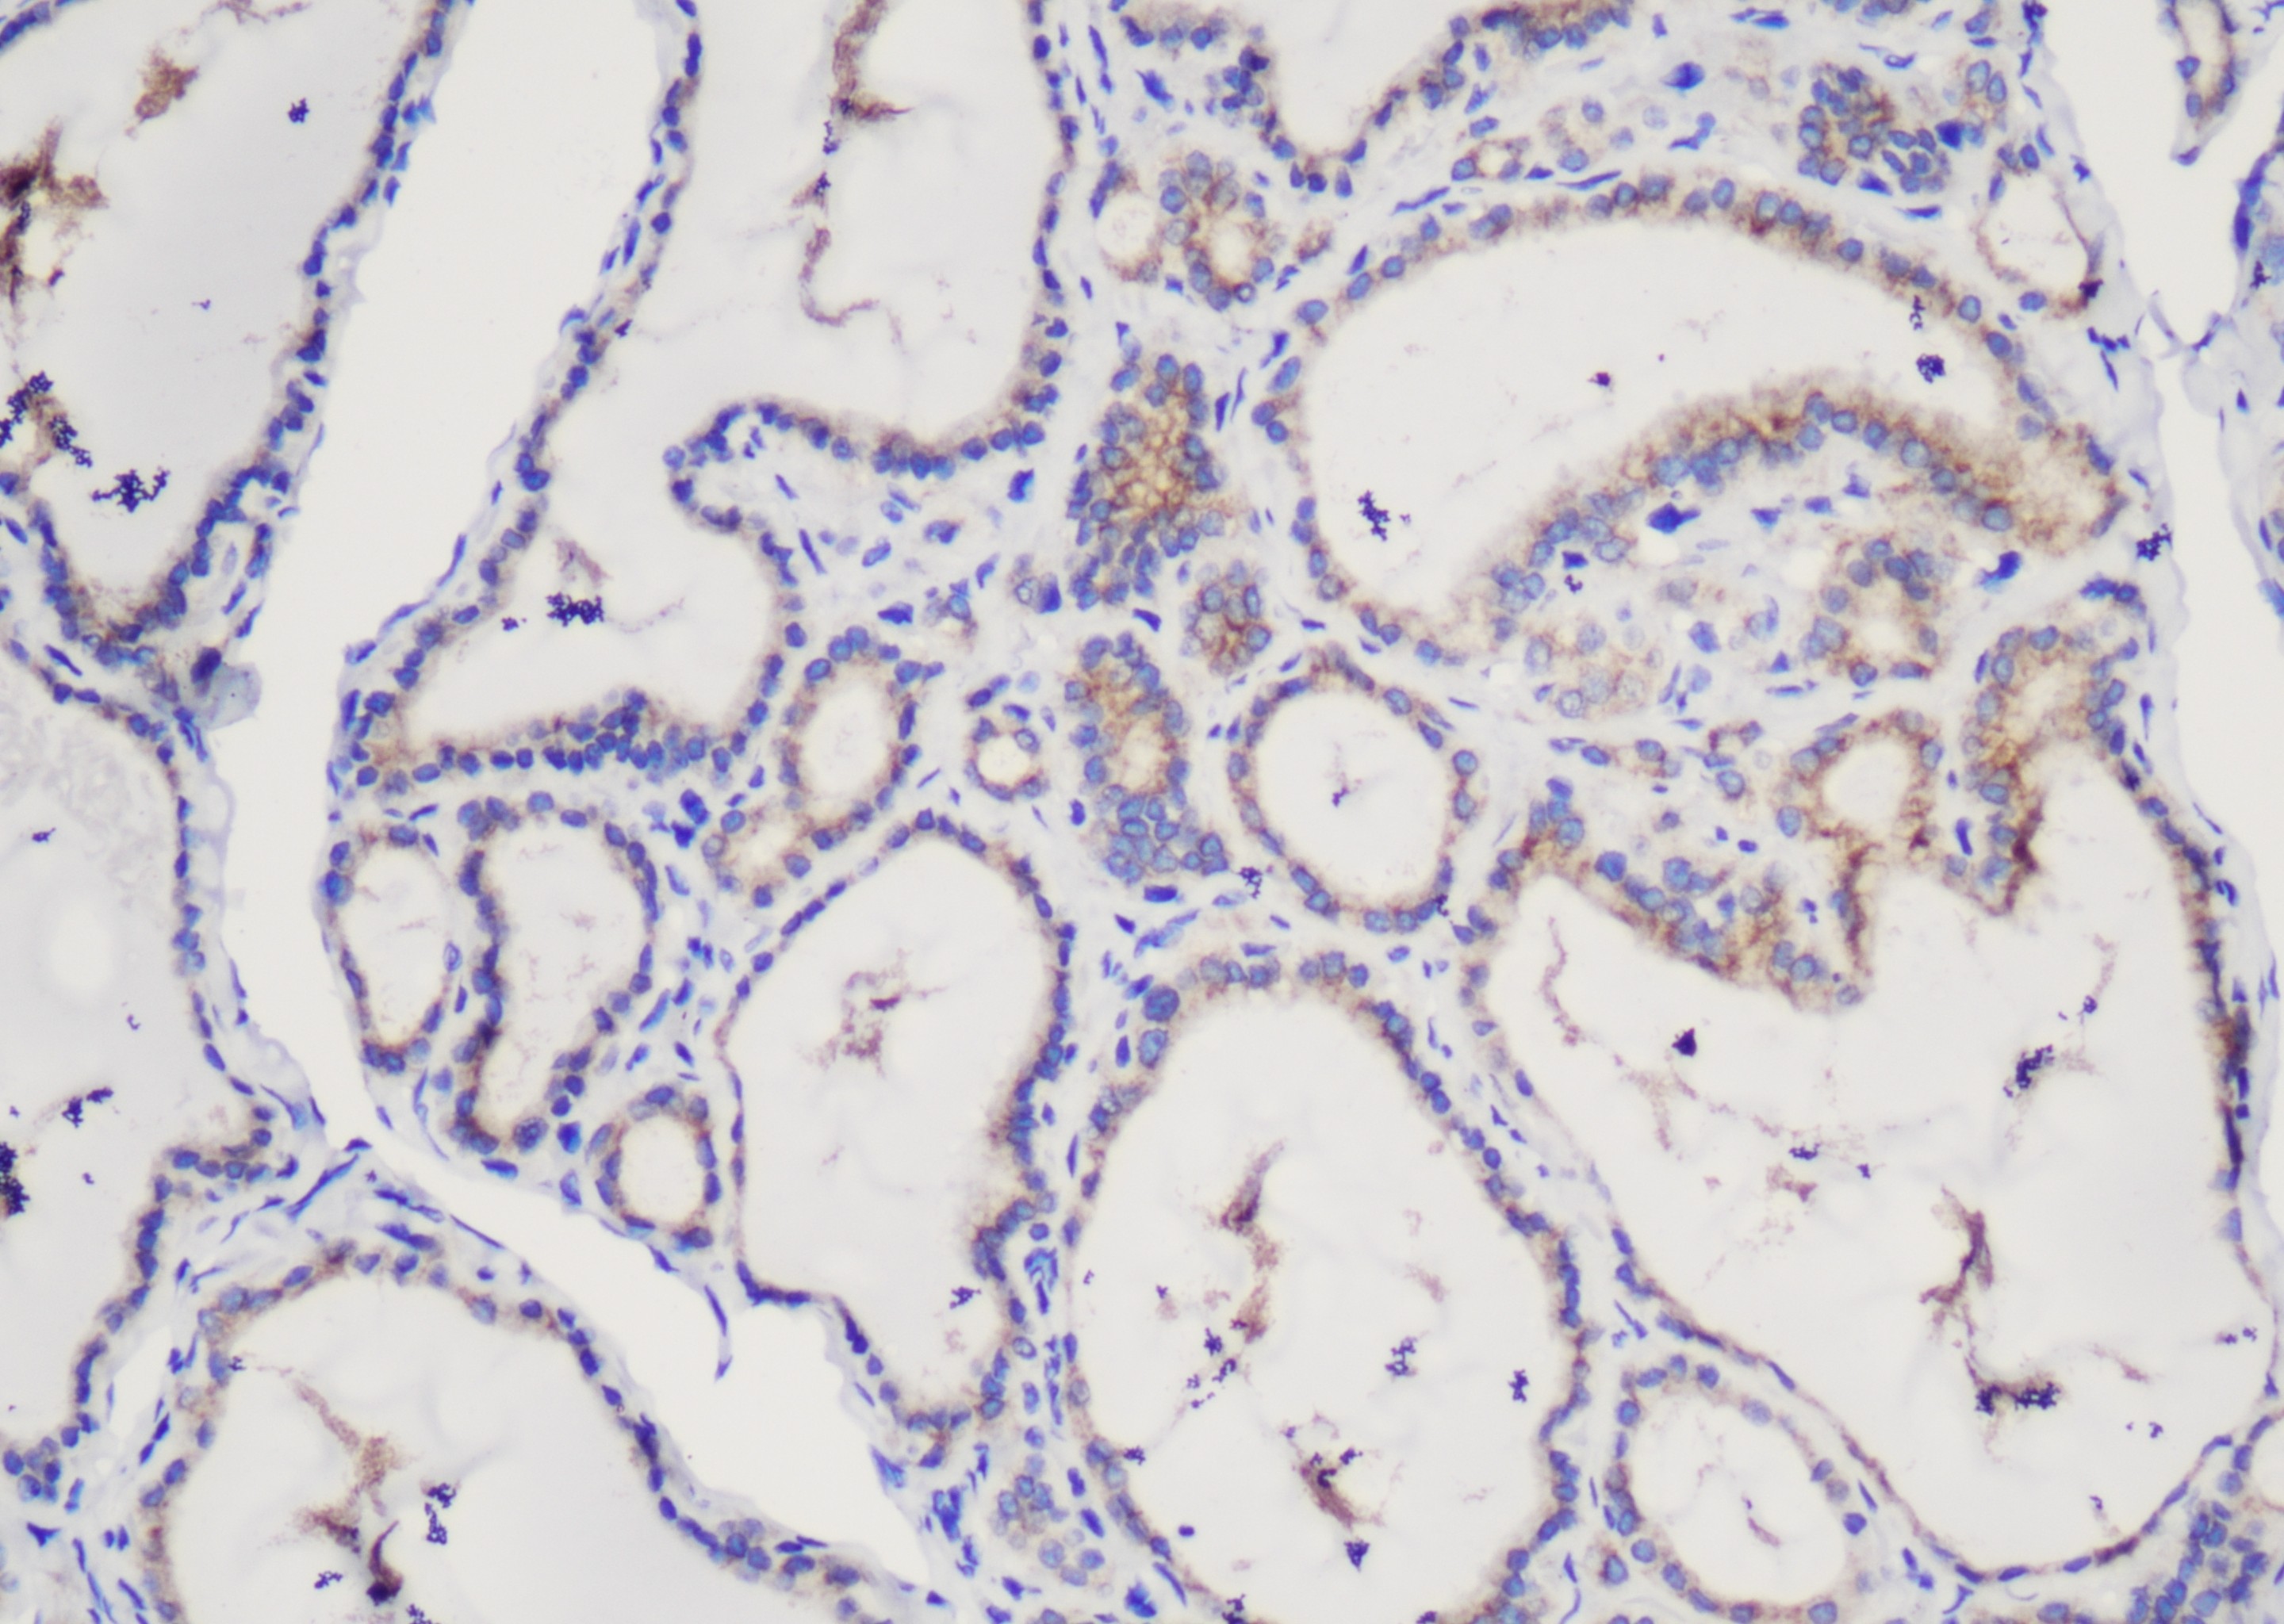

AMACR/p504s

AMACR/p504s(Alpha-methylacyl-CoA racemase,a-甲基酰基-辅酶A消旋酶)是体内的某些脂肪酸 代谢的关键酶,存在于肝脏、涎腺、肾脏和胰腺等组织中。AMACR/p504s 可用于前列腺癌、乳头状肾细胞癌的诊断,结直肠癌和小肠腺癌的鉴别,胃上皮内瘤变的辅助诊断,Barrett食管异型增生的辅助诊断等。